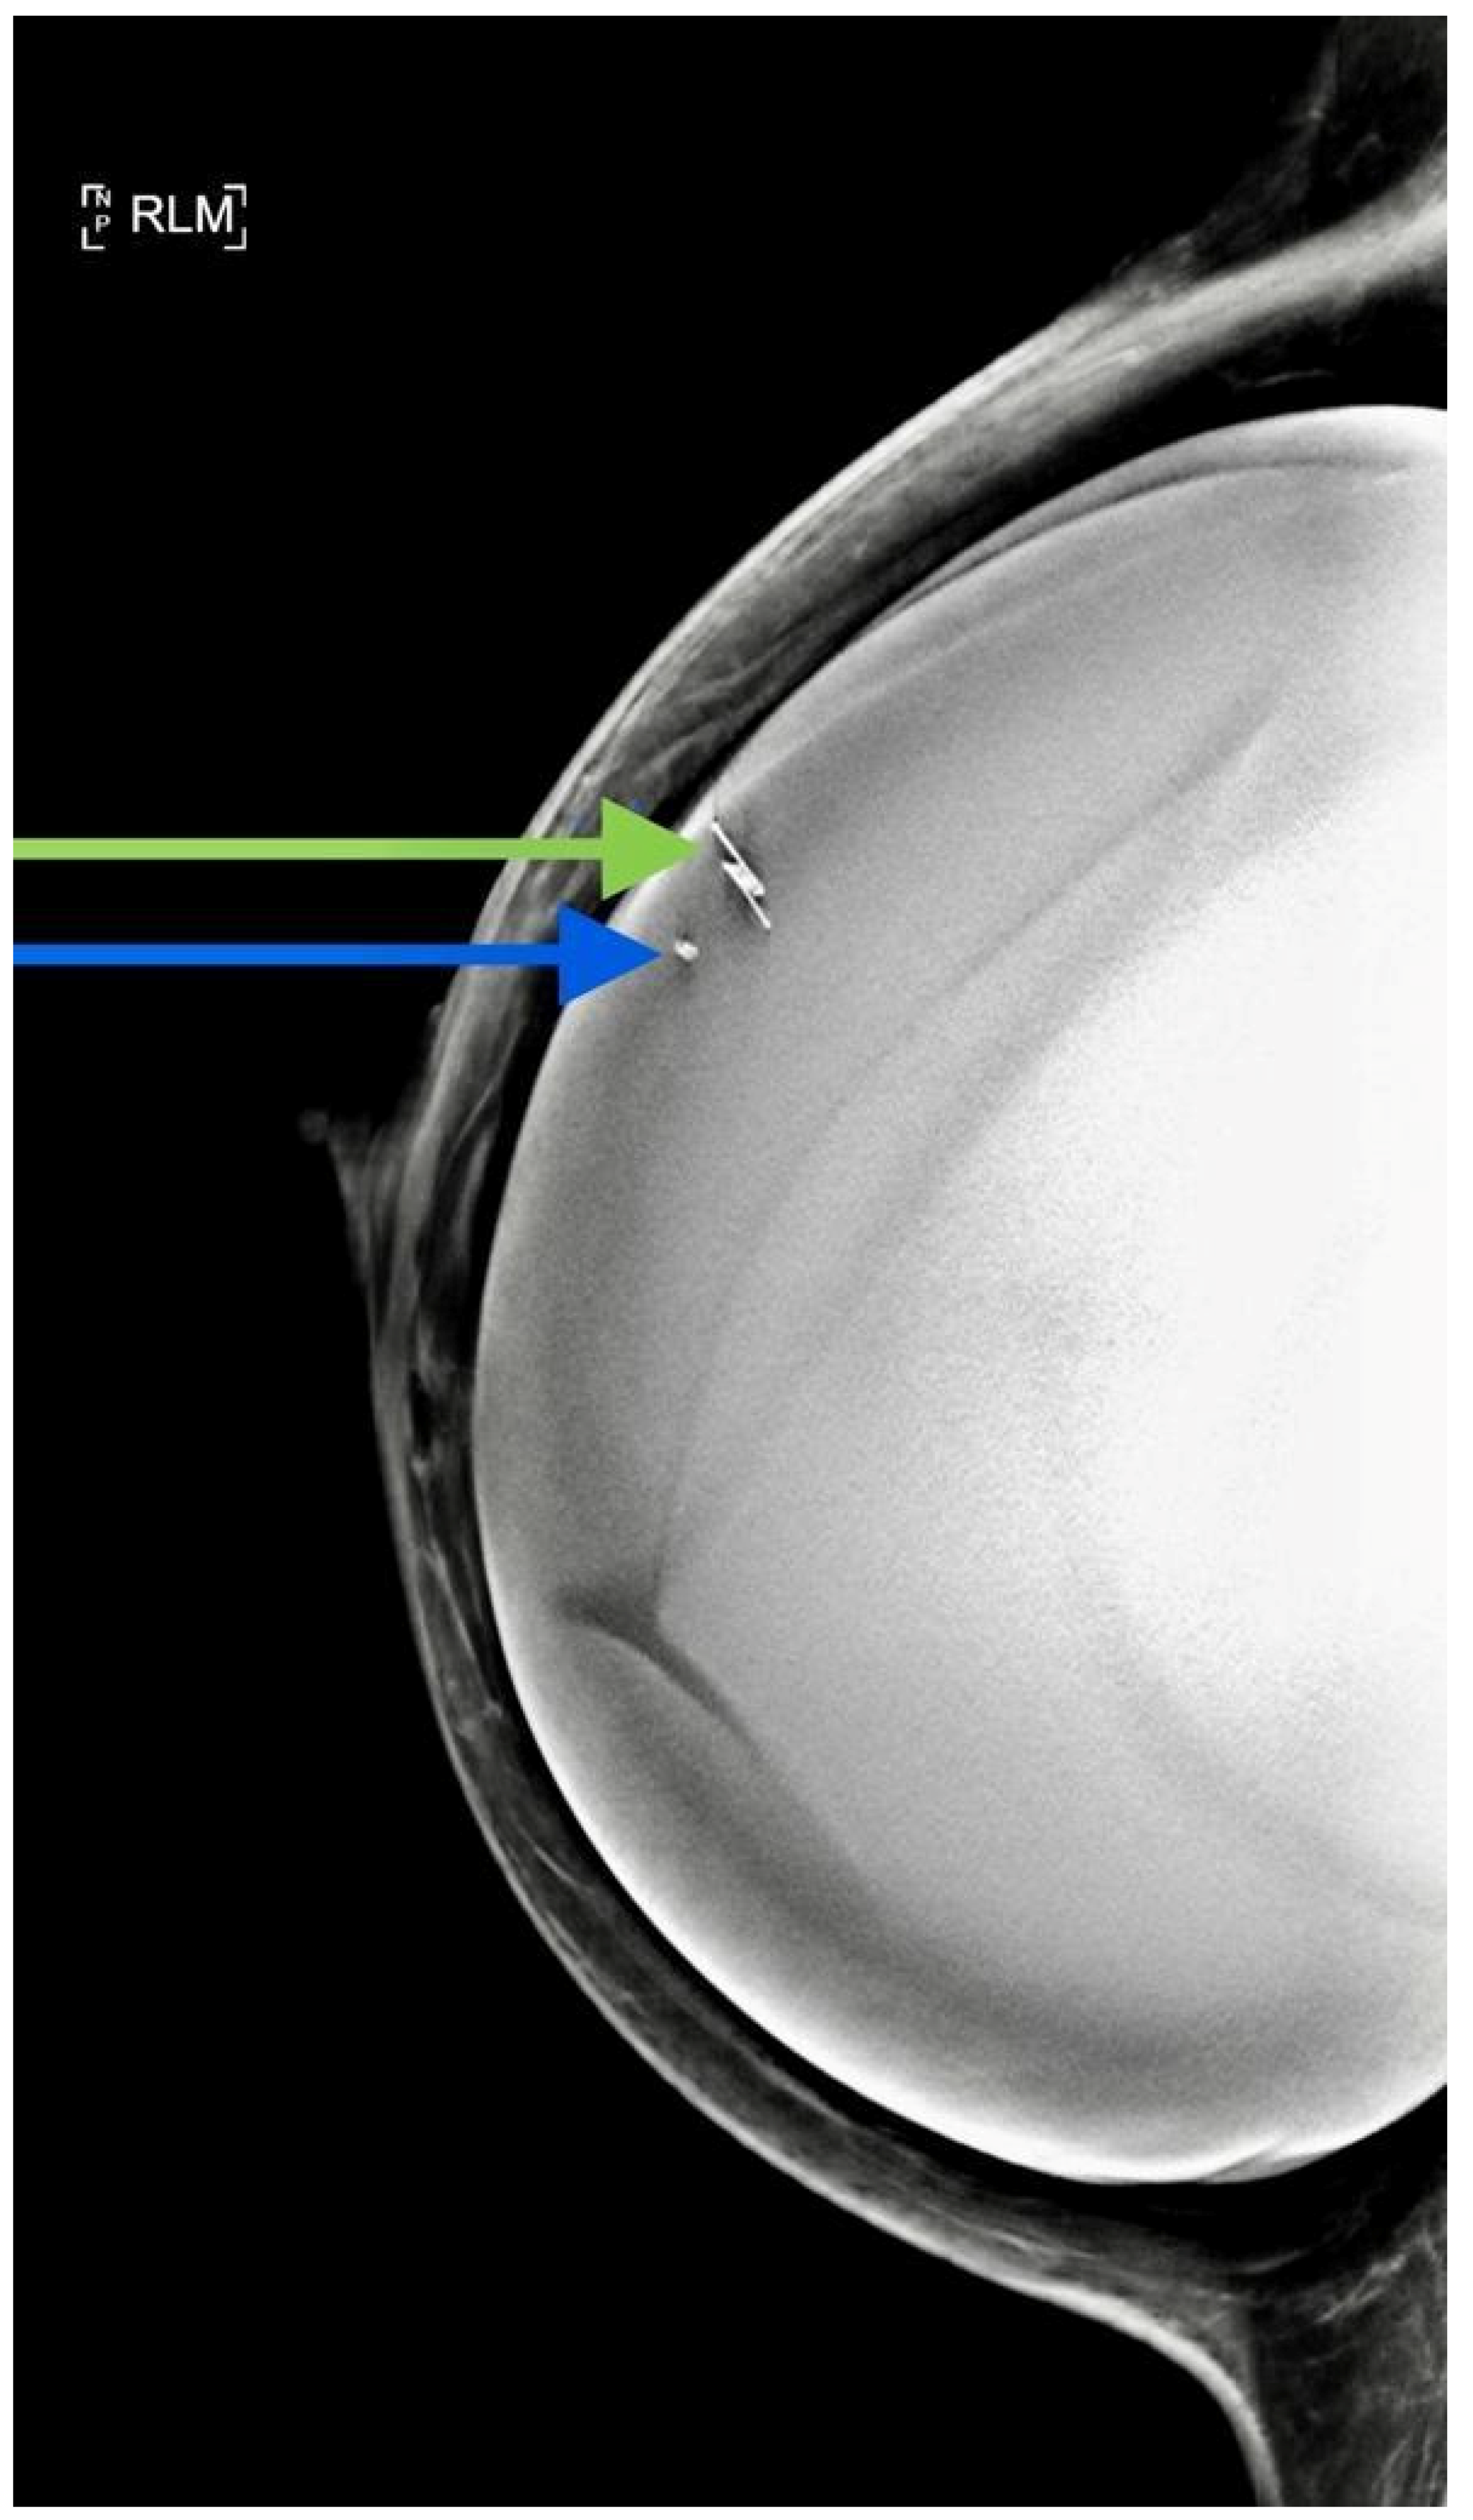

- Tayeh, S.; Muktar, S.; Heeney, J.; Michell, M.J.; Perry, N.; Suaris, T.; Evans, D.; Malhotra, A.; Mokbel, K. Reflector-guided localization of non-palpable breast lesions: The first reported european evaluation of the savi scout(r) system. Anticancer Res. 2020, 40, 3915–3924. [Google Scholar] [CrossRef] [PubMed]